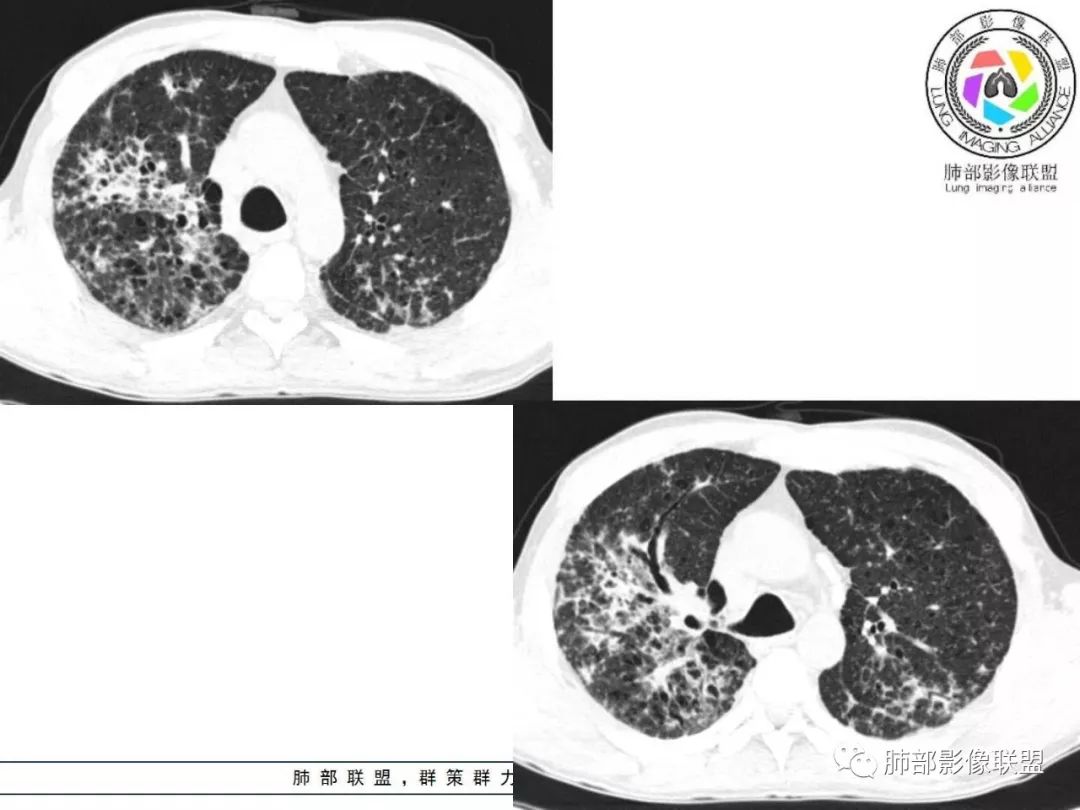

双肺间质性病变,中央间质增厚,胸膜下间质增厚,左侧胸膜肥厚,胸廓变小,肋间隙变窄。

对,大的支气管血管周围

胸部CT:两肺弥漫病灶,磨玻璃影,少许实变,部分累及胸膜,磨玻璃区可见囊?少许胸腔积液,两肺可见结节,支气管血管束增粗,小叶间隔增厚,支气管走形有扭曲扩张,可见纤维化。气肿、大泡。考虑:感染性病变,PCP?查下HIV,CD4,G等。鉴别结核、结缔组织病肺浸润。

病灶呈片状磨玻璃密度影,呈典型的烟花征。磨玻璃影密度偏高,有网结节样改变,与正常肺实质分界清楚,且常见相对高密度的勾画。

烟花征分为3肿类型:晕征、反晕征及均匀分布。

病变一般沿血管支气管束分布或小叶分布,一般上肺多于下肺(这与常见继发性肺结核分布相若)。

常会伴有其他继发性肺结核病灶,如斑片影、结节影,树芽征,新旧不等改变。

2. 肺气肿背景(小叶中心性肺气肿);双肺多发病灶整体沿血管支气管束及胸膜下分布,以上叶及下叶背段分布为主,有实变及GGO,边界清楚,有树芽,小叶间隔及中央间质增厚,叶间裂见到多发结节,部分支气管不规则牵拉扩张,提示病灶纤维化明显,结合临床病史,考虑病灶为间质性感染,肺门及纵隔内有钙化淋巴结,小叶间隔结节,考虑淋巴道增值性疾病可能,综合常规要怀疑间质性肺结核。